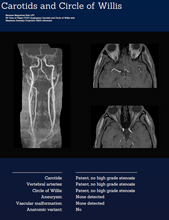

• Brain aneurysms or lesions

The MRI is a non-invasive scan that can detect early signs of tumours, cysts, aneurysms, organ irregularities, joint inflammation, spinal issues, and other structural abnormalities, often before symptoms develop.